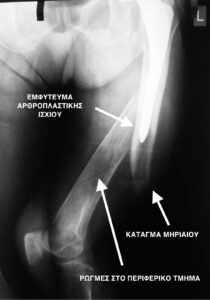

Τα περιπροθετικά κατάγματα, είναι κατάγματα που συμβαίνουν γύρω από ένα εμφύτευμα αρθροπλαστικής. Ειδικότερα το κάταγμα βρίσκεται σε γειτνίαση με το εμφύτευμα (κοντά ή λίγο μακριά του), ή ακόμη και ανάμεσα σε δύο εμφυτεύματα. Δηλαδή ύπαρξη ενός κατάγματος στο μηριαίο οστούν όταν πιο πάνω υπάρχει μία αρθροπλαστική ισχίου, και πιο κάτω στο ίδιο οστούν μία αρθροπλαστική γόνατος .

- Περιπροθετικό κάταγμα. Κάταγμα του οστού σε γειτνίαση με ορθοπεδικό εμφύτευμα. Διακρίνεται το κάταγμα κάτωθεν του εμφυτεύματος.